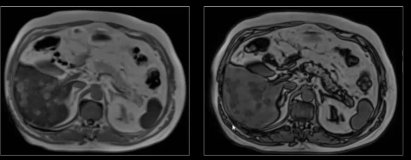

As lesões focais hepáticas na imagem são suspeitas para metástases.

Sequências GRE em fase/fora de fase.

Falso.

As lesões na imagem correspondem a esteatose multifocal/multinodular.